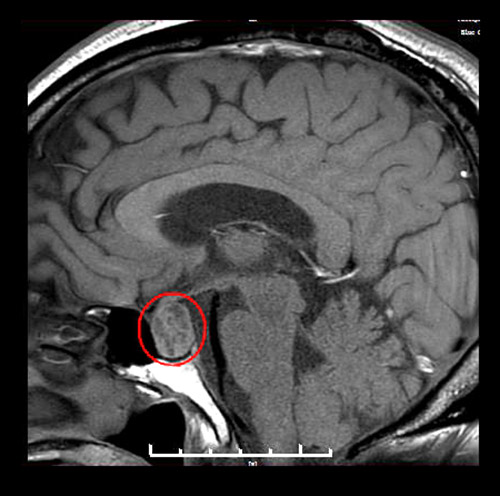

▲术前MR影像:垂体大腺瘤,超蝶鞍生长

神经外科执行主任潘仁龙详细了解了患者的病情,为其完善各项检查。鞍区MRI平扫+增强显示,患者蝶鞍稍扩大,鞍底骨质下陷;鞍内垂体上缘膨隆,腺垂体中央见一枚类椭圆形异常信号,直径约1.8*1.4厘米。综合各项检查结合临床,王老伯确诊为垂体大腺瘤(1~3cm的叫做大腺瘤)。